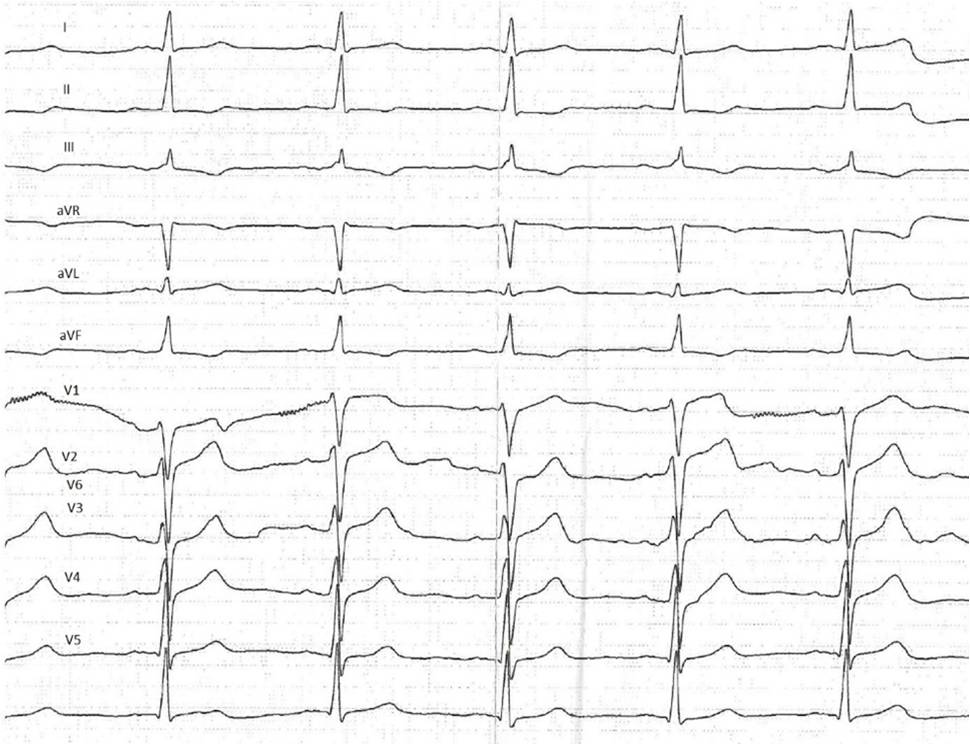

ECG: with sinus rhythm, alterations of the myocardium of the lower wall of the LV were recorded as downsloping ST segment depression with negative T wave in III, aVF leads (Figure 1).

Fig. 1. Electrocardiogram of patient L. on admission 2014, November 28.